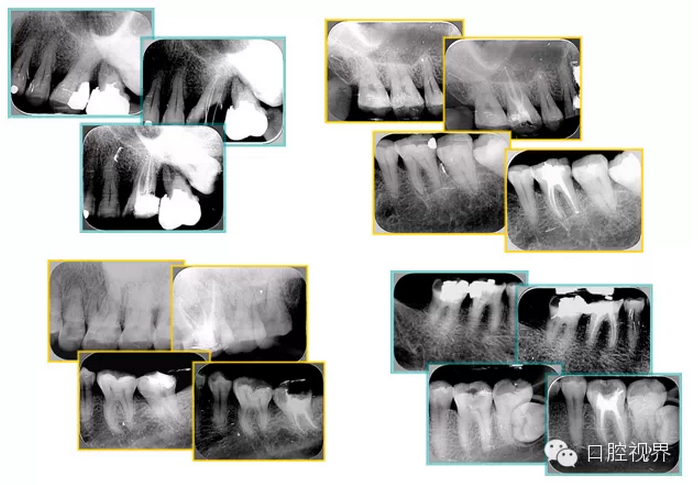

2. X 線片

共有 4 張 X 線片,分別是術(shù)前、診斷絲 、主牙膠尖確認、術(shù)后。

( 1 )術(shù)前:術(shù)前 X 線片用來了解牙齒的大概情況。術(shù)前預(yù)期為多根牙時 X 線片應(yīng)偏頭拍攝。

( 2 )診斷絲:根據(jù)術(shù)前 X 線片進行開髓、根管的初步預(yù)備后,需要插入診斷絲,用來指示工作器械位置。常用 10 號或 15 號擴大器作為診斷絲插入牙髓腔。

( 3 )主牙膠尖確認:通過術(shù)前預(yù)期和診斷絲診斷,明確工作長度、牙根走向,進行根管預(yù)備。之后應(yīng)進行主牙膠尖(中銼)確認,已明確根管是否適合充填。

( 4 )術(shù)后:觀察治療效果。